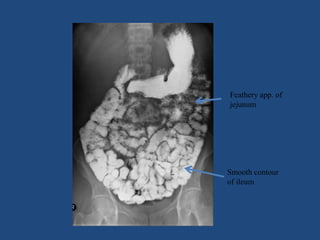

BARIUM MEAL FOLLOW THROUGH

• Demonstrate the whole of small bowel from

duodenal flexure to ileocaecal junction

TECHNIQUE

• Following drinking contrast(50-100%w/v)

patient lies in prone or on right side until ba

has left the stomach

• AIM- to produce continous column of Ba in

small bowel

• spot films may be made of any loops or

segments of bowels

WELL PERFORMED BARIUM MEAL

• Entire BL should be included in each

radiograph

• Stomach & duodenum should be documented

in initial films

• Time marker should be clearly visible

• Ileocaecal j/n should be well visualised

Feathery app. of

jejunum

Smooth contour

of ileum